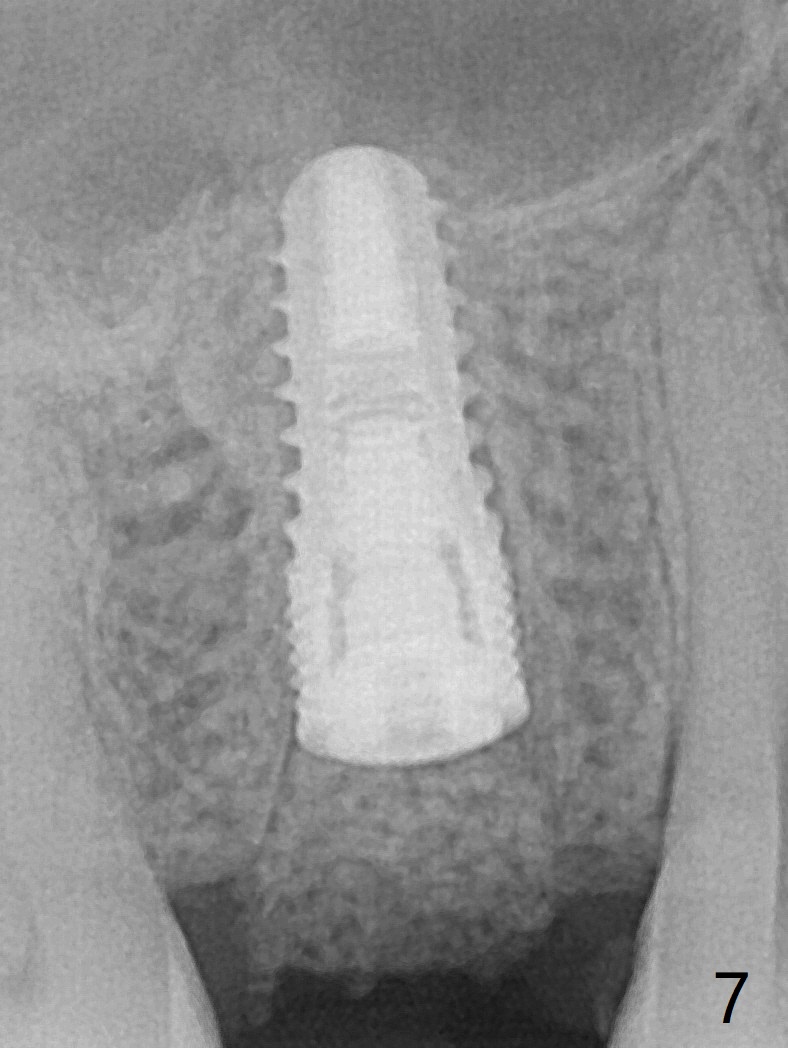

40岁女右上5近中龈下龋齿(图一),要求拔除植牙,上颌窦底板已经破坏穿孔,但是窦膜完整(图二)。清创后,放置PRF膜和粘性骨粉,用挖匙和上颌窦充填器尽量往上面推。然后放置导板,使用2.2x7.3 和3.0x7.3毫米钻头完成钻洞,可能无意中把骨粉推入上颌窦,之后利用报废植体(图三,四)完成提升,同时修补根尖缺损(利用之前放置的骨粉,图四:*,与图五(术前)对比)。当报废植体取出时,植牙窝已经形成,再放入少量骨粉,植入同样大小(之前扭力高)正式植体(不同品牌,图六,七),这时扭力低,放置愈合帽和骨粉(图七,八),以及6-9个月吸收膜,使用牙周胶水固定(图九),最后牙周敷料。术中术后几个小时没有上颌窦膜破裂迹象。术后一周牙周敷料松动,造成不适,去除时,膜好像粘附于敷料一起去除,骨粉暴露(图十),使用树脂敷料固定。后者术后一个月去除,因为局部有臭味。术后4个月切开放置愈合基台(图十一),术后五个月放置修复基台(图十二),使用塑料袖取模。术后5.5月同时放置牙冠和基台,十分顺手,口内粘固,之后同时取出,除去多余粘固剂,然后拧紧30Ncm(厂家推荐35 Ncm),一切非常顺利,觉得拍摄X光片是多余的。美中不足的是开孔(access hole)偏腭侧(图十二;由于自由手植入植体,与设计对比)。